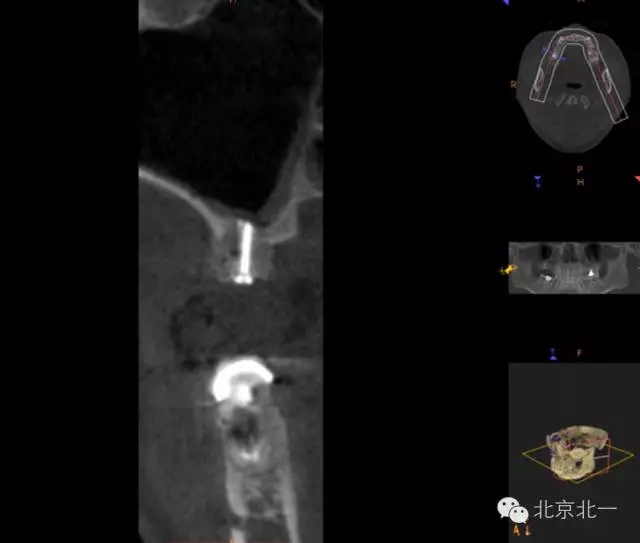

圖四:取骨區(qū),下頜智齒位置,取骨工具用超聲骨刀。

圖十九:手術(shù)后當(dāng)天CBCT

圖二十-二十二:ONLAY植骨半年后

供區(qū):口腔常用取骨部位:下頜角區(qū),頦部,上頜結(jié)節(jié)。頦部因為術(shù)后可能出現(xiàn)感覺異常,現(xiàn)已少用, 植骨區(qū)不大可選擇下頜角區(qū), 并發(fā)癥少。 如果取骨量大,可選擇髂骨區(qū)。